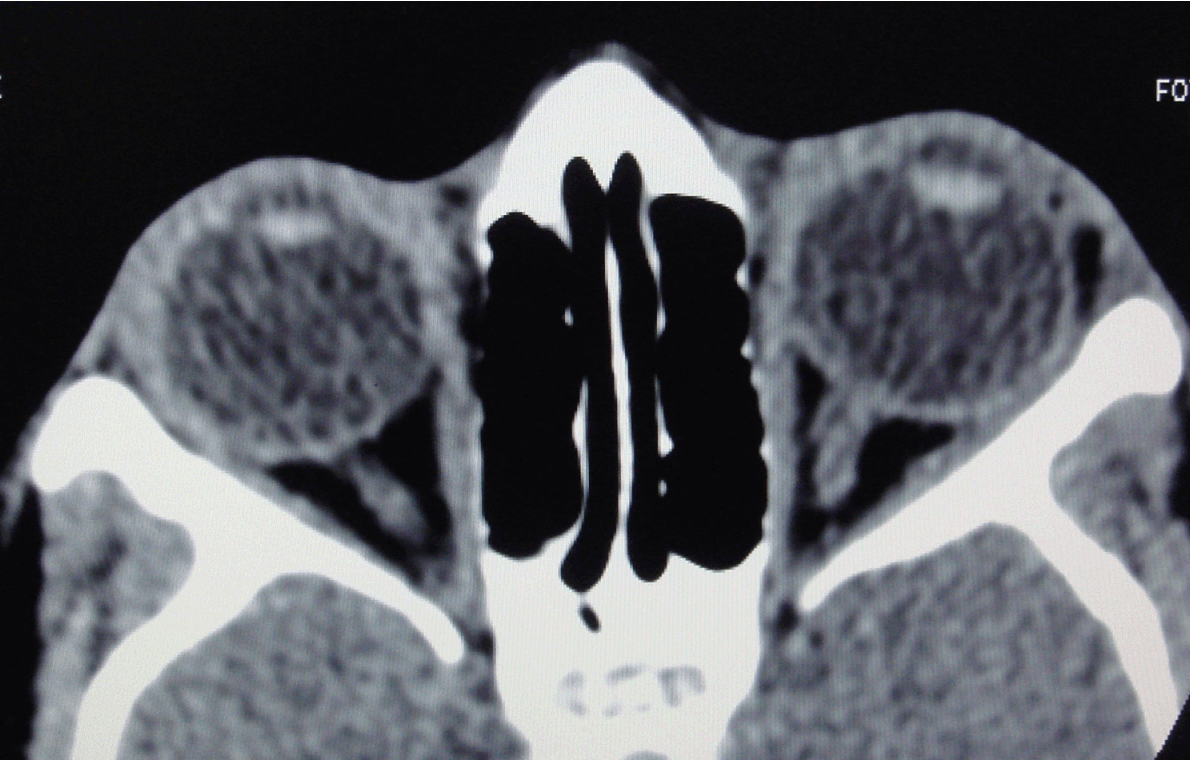

A 12-year-old Asian girl presented to our department for computed tomography (CT) scan of orbits for evaluation of ocular dermoid cyst. The child was born to non-consanguineous parents with uneventful prenatal and antenatal period. There was no relevant family history. Her mental status was normal and there was no evidence of developmental delay. Left limbal dermoid cyst measuring 0.5x0.5 cm with hair follicles was seen at 5 o’clock position since birth, (Figure 1A-B) which is painless and not increasing in size. A dermal tag was seen at the lateral canthus of the left upper eyelid. (Figure 1A) There was no redness or discharge from the eyes and ocular motility was normal bilaterally. Her visual acuity was normal (6/6). An accessory preauricular tag was seen on the left side. (Figure 1C) Audiological examination shows no evidence of hearing impairment. Intraoral examination revealed malocclusion of lower dentition. (Figure 2) Cardiovascular system and central nervous system were normal. Hematological investigation showed hemoglobin 11.9 g/dL, total leukocyte count (TLC) 8500/μL, neutrophils 38%, lymphocytes 48%, eosinophils 15%, monocytes 5% and platelet counts 274x103/μL. Routine and microscopic urine investigation were within the normal limits. No abnormality was seen on plain radiograph (antero-posterior and lateral views) of cervical and thoracic spine. The CT scan of orbits showed a hypodense lesion of fat attenuation measuring 0.8x0.5 cm on the lateral aspect of the left orbit abutting the lateral margin of the globe, suggestive of dermoid cyst. (Figure 3) Another small similar lesion measuring 0.5x0.5 cm seen at the left limbal region (suggestive of dermoid cyst). Grayscale ultrasonography (USG) of left orbit showed a small echogenic lesion at the limbus. (Figure 4) Clinical and radiological features were suggestive of Goldenhar syndrome. Pediatric consultation was also done to rule out any systemic associations. She was referred to dentist for needful correction of the maloccluded teeth. Surgical excision of the dermoid cysts was done. Postoperative period was uneventful. | ||||||